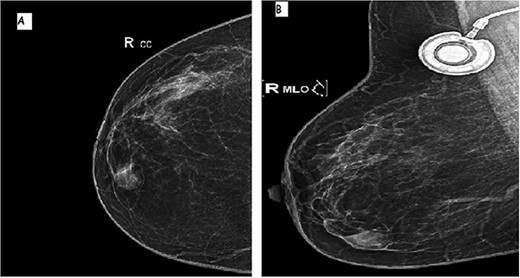

A 64-year-old female with prior history of treated left breast carcinoma, presented to the department of gynecology with a palpable mass inferior-internal quadrant of right breast. Mammography showed a well-circumscribed mass with focally indistinct margins, there were no calcifications (Fig. 1). On ultrasonography, the mass had regular contours with heterogeneous echogenicity, measuring 8 × 5 mm. They were no axillary palpable lymph nodes. Ultrasound-guided core biopsy was performed and the specimen was sent to our laboratory for pathological examination.

Mammographic image of the right breast, front (A) and side (B) views: inferior-internal quadrant mass of medium density, oval and circumscribed with partially indistinct margins without calcifications.